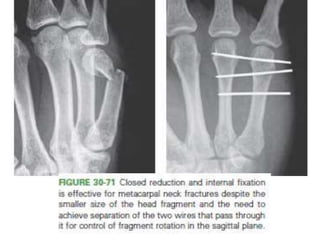

Closed Reduction and Internal Fixation

• Isolated metacarpal fractures not meeting the criteria for

nonoperative.

• Extra-articular and intra-articular fractures

Closed Reduction andInternal Fixation • Isolated metacarpal fractures not meeting the criteria for nonoperative. • Extra-articular and intra-articular fractures • anatomically reducible and stable to the stress of motion